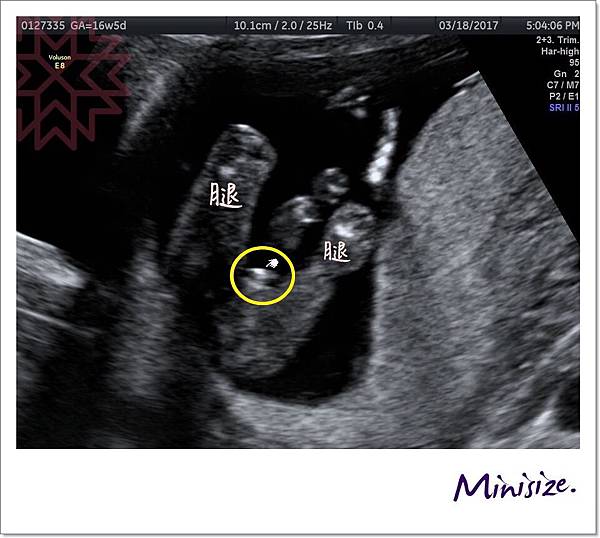

知道你們期待娃兒性別

寶寶也大方展現私密部位

一次讓爸爸媽媽看個精光不後悔

黃色圓圈處就是帶點亮光的小雞雞

寶寶:我是個小男生!!